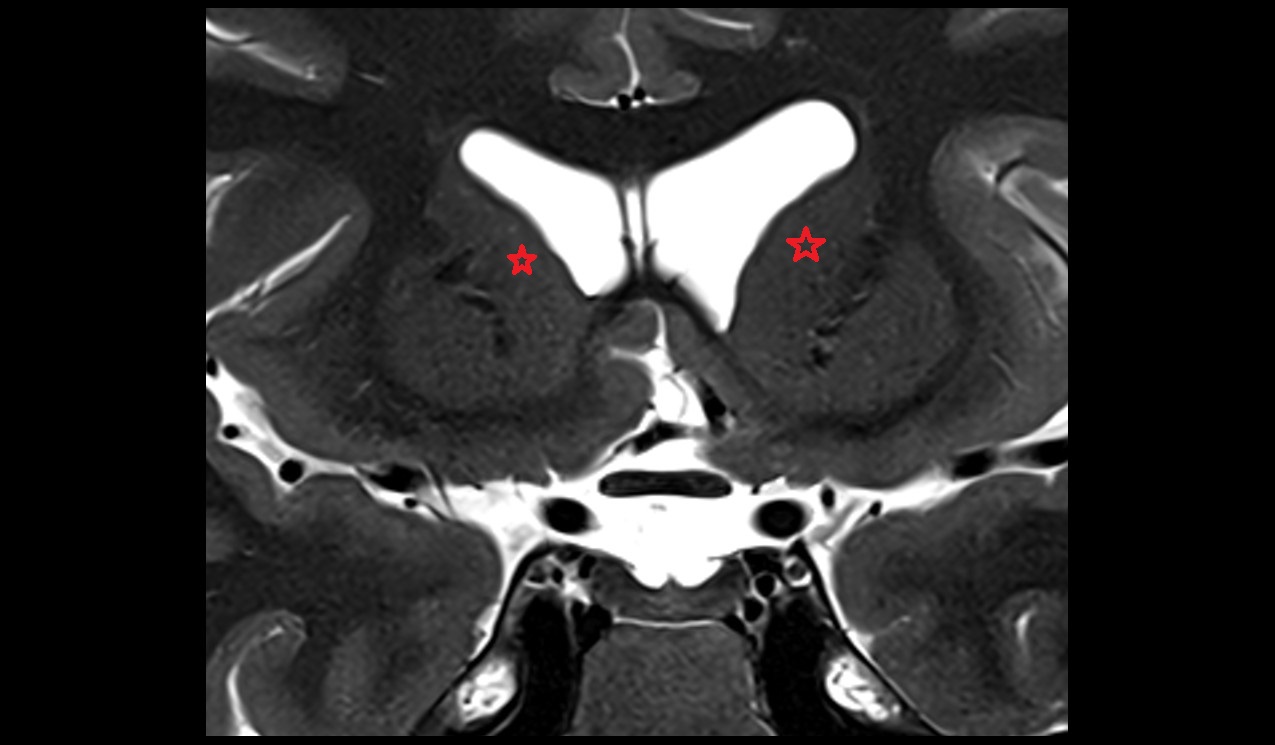

- Hippocampal body

- Hippocampal head

- Hippocampal tail

- Body of hippocampus

- Head of hippocampus

- Tail of hippocampus

- Hippocampus